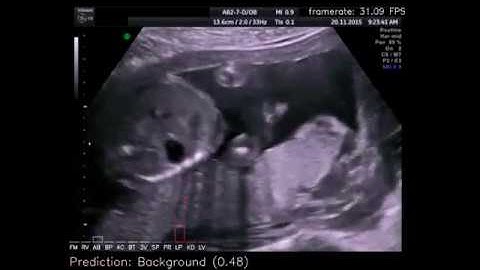

Real-time fetal biometrics using deep convolutional neural networks